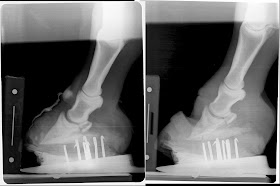

Below are radiographs from immediately post deep flexor tenotomy and 60 days post tenotomy. Noteworthy change on both are additional sole depth under tip of coffin bone. However continued remodelling of the tip of the coffin bone and a slight increase in palmar angle on the left hoof are suggestive that the dorsal portion still fails to grow at a rate similar to the palmar portion. This hoof suffered more damage as it was the "club". Deep flexor tenotomy was not performed at the recommended time. Significant pathology was identified within 5 days of onset of acute laminitis but owner refused tenotomy at that time.